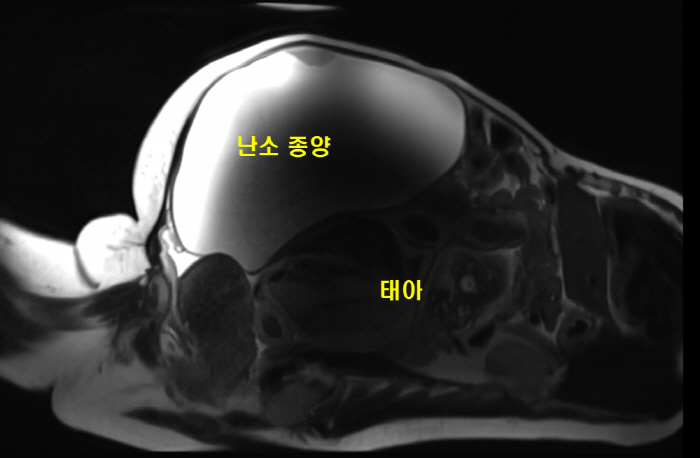

[스포츠조선 장종호 기자] 10kg에 달하는 난소 종양이 있는 여성이 자궁외 임신 상태에서 건강한 아기를 출산해 화제다.

기쁨도 잠시, 정밀 검사 결과는 극히 드문 형태의 자궁외 임신 중 하나인 복강임신이었던 것.

자궁외 임신이란 수정란이 자궁이 아닌 다른 곳에 착상하는 것을 말하며 복강임신은 말 그대로 복강내에 임신이 된 상태로 매우 드물게 발생하며 일반적인 자궁외 임신보다 치사율이 더 높은 것으로 알려져 있다.